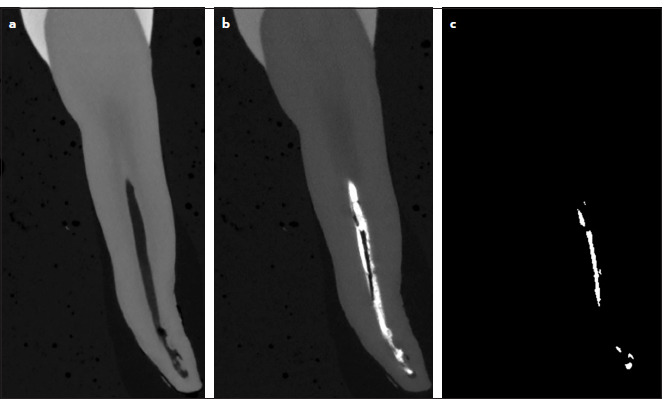

Methods: Human maxillary premolars (n=33) were shaped, cleaned and root-filled using the cold lateral condensation (CLC) technique. Voids were identified using either individual tomographic slices or the new proposed protocol in which: (1) pre-obturation XMT slices were used to identify the coordinates of the canal space; (2) the post-obturation data sets were aligned to the pre-obturation data sets; (3) the voids were identified as voxels with a grey level below a set threshold after subtraction of pre-obturation from post-obturation data sets. A comparison of the voids from these two methods was made.

Results: The visual inspection of slice by slice of the scanned data resulted in full agreement between the tomographic slices and the results gained from the proposed protocol. This confirmed that this protocol provided an automated, effective and accurate method for detecting voids in root-filled canals.